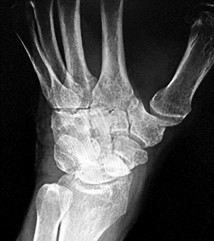

A 30-year-old male presents with a comminuted intra-articular fracture of the first metacarpal base.

What are the primary deforming forces acting on the metacarpal shaft in this injury?

Explanation

In intra-articular fractures of the thumb metacarpal base (Bennett and Rolando fractures), the palmar ulnar fragment remains attached to the anterior oblique ligament (beak ligament). The metacarpal shaft is pulled proximally, dorsally, and radially by the abductor pollicis longus (APL), while the adductor pollicis (AP) pulls the metacarpal head into the palm, resulting in the classic supination and adduction deformity.